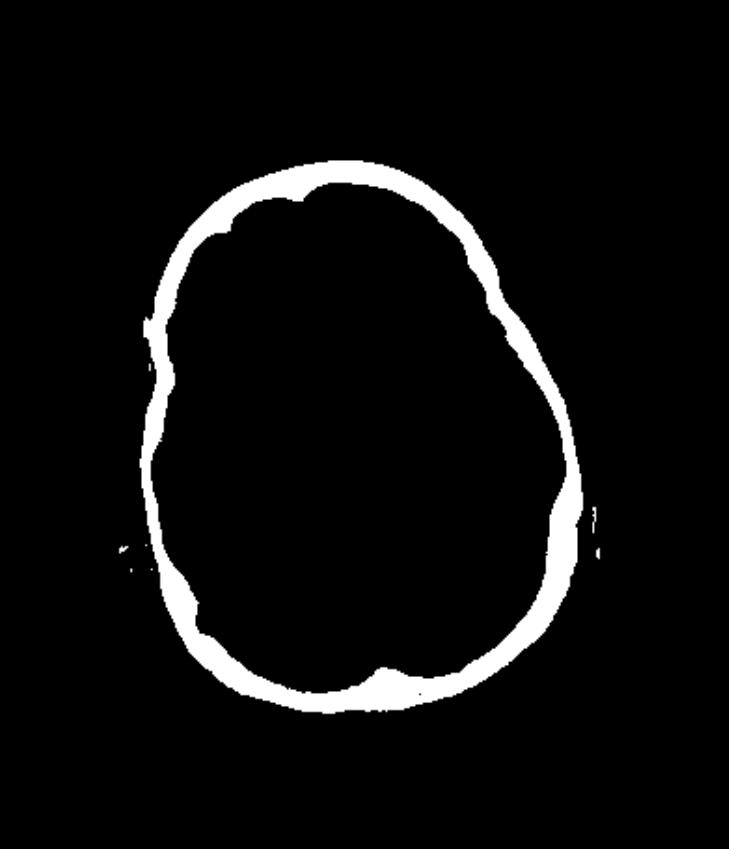

Refer to caption

(b) Bone Removal Mask (a)

The pipeline we propose receives a CTA image as input, an example of which is shown in Fig. 2(a). Alongside the CTA data, a brain atlas (shown already registered to an example in Fig. 2(c), a mean brain over a patient populations) (Kemmling et al., 2012) together with the corresponding vessel atlas (Forkert et al., 2012) (accordingly transformed, shown in Fig. 2(d)) is given. The latter atlas is a volume representing the existence of voxels belonging to a vessel by means of a probability value, whereby it emphasizes on the arterial branches close to the Circle of Willis. In a first step, all bone structures are removed, as indicated in Fig. 2(a), using a method by Chen et al. (2020) which segments those bone structures in CTA scans. An example is shown in Fig. 2(b) which is the bone segmentation of the slice shown in Fig. 2(a). The CTA volume is not only forwarded to the bone removal but also used to register the brain atlas onto in Fig. 2(b). The non-rigid (elastic) registration is based on Chefd’Hotel et al. (2002)’s method specifically designed to register multi-modal volumes. The resulting deformation field is used to transform the vessel atlas (Forkert et al., 2012) in step Fig. 2(c) into the CTA coordinate system. Tubular structures of the bone-free CTA scan, resulting from Fig. 2(a), are enhanced using the Frangi filter (Frangi et al., 1998) (two scales, σ1=1.00subscript𝜎11.00\sigma_{1}=1.00, σu=1.50subscript𝜎𝑢1.50\sigma_{u}=1.50) exemplarily shown in Fig. 2(e). The filter response is masked in Fig. 2(e) with the vessel atlas, which is binarized with a relative threshold of t1=0.5%subscript𝑡1percent0.5t_{1}=0.5\% (of the maximum value) followed by dilation (with a kernel size in z,y and x of 11, 7 and 7, respectively). Fig. 2(f) shows the result of the vessel masked Frangi response, which is thresholded with t2=4subscript𝑡24t_{2}=4. Values below that threshold are suppressed to zero, values above are kept with the original values. With this step, noise is being reduced which stabilizes the subsequent steps, like the slice-wise circle based Hough transformation in step Fig. 2(f)(canny threshold = 10, accumulator threshold = 1, min distance = 5, min radius = 0, max radius = 5 and accumulator threshold = 1). The goal of the Hough transformation is to identify circle-shaped structures in the given slices, however, as shown in Fig. 2(g) many centerpoints of the detected circles do not match with the preliminary vessel tree segmentation. Hence in the next step, the mask used for the Hough transform is reused again, to mask out in step Fig. 2(g) all centerpoints which do not align with the segmentation. The example shown in Fig. 2(g) originally has 6747 centerpoints in total, reduced to 1375 by the masking, the result of which is shown in Fig. 2(h). The remaining points are used as seed points for region growing in Fig. 2(h). The region growing segments all voxels connected to the seed points, whose intensity differs no more than ±5%plus-or-minuspercent5\pm 5\% from the average intensity of the seed point voxel values. The result is a preliminary segmentation which only includes vessel segments represented in the original vessel atlas. As will be described below, this mask is used for labeling. The result is shown in Fig. 2(i). In order to segment all vessels, especially more distant vessel structures, the segmentation mask of step Fig. 2(h) is transformed into seed points which are used for the final region growing in Fig. 2(h) segmenting every connected voxel with a value in the range of 130 HU to 1500 HU. Its result is the final segmentation, shown in Fig. 2(j). The whole pipeline has been implemented in MeVisLab 3.4, MeVis Medical Solutions AG, Bremen.